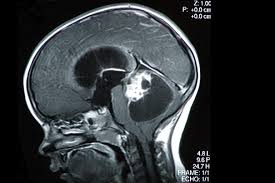

Brain tumor diagnosis in children A seizure is sometimes the first sign of a brain tumor, but it can happen at any stage. Key points about a brain tumor in a child. It can be tough to know what to say to a parent who is facing a child's health crisis. For children with common headaches, a red flag that it might be something more serious than a simple migraine would be if the headaches continued to get worse over time, becoming either more severe or more frequent.

World Cancer Day 4 Month Old Beats Brain Cancer Mom Shares Emotional Video Times Of India from static.toiimg.com A brain tumor can cause symptoms by directly pressing on the surrounding parts of the brain that control certain body functions, or by causing a buildup of spinal fluid and pressure throughout the brain (a condition known as hydrocephalus). But so many children have headaches that a tumor is still a very rare cause for a headache. General signs and symptoms caused by brain tumors may include: For children with common headaches, a red flag that it might be something more serious than a simple migraine would be if the headaches continued to get worse over time, becoming either more severe or more frequent. But a lot of children have headaches, and most of them don't have a brain tumor. The symptoms you are experiencing are linked to the location of the tumor in your brain. Headaches are present in 70% of children with brain tumors; If your child has been diagnosed with a brain tumor, know that your family doesn't have to go through this alone.

But so many children have headaches that a tumor is still a very rare cause for a headache. The symptoms you are experiencing are linked to the location of the tumor in your brain. If the tumor affects the optic pathway, which is responsible for sight, the child may experience vision changes. It's normal for you, your family, and your friends to need help coping with the feelings that such a diagnosis can bring. Most importantly, close examination of your eyes using an ophthalmoscope can reveal swelling, which is evidence of increased pressure in the brain caused by a brain tumor. The key to a tumor's symptoms really depends on its location, says theodore schwartz, md, a neurosurgeon with the weill cornell brain and spine center. Has your head been hurting a lot lately, and you're wondering if you might have a brain tumor? The signs and symptoms of a brain tumor vary greatly and depend on the brain tumor's size, location and rate of growth. Signs or symptoms vary depending on a child's age and the location of the tumor, but may include: Of course, it is not impossible to detect signs and symptoms of a brain tumor, and here we will explain some common signs you can have. Brain tumor diagnosis in children It is common to have concerns about brain tumor treatments or surgery, plus; Sometimes, people with a brain tumor do not have any of these changes.